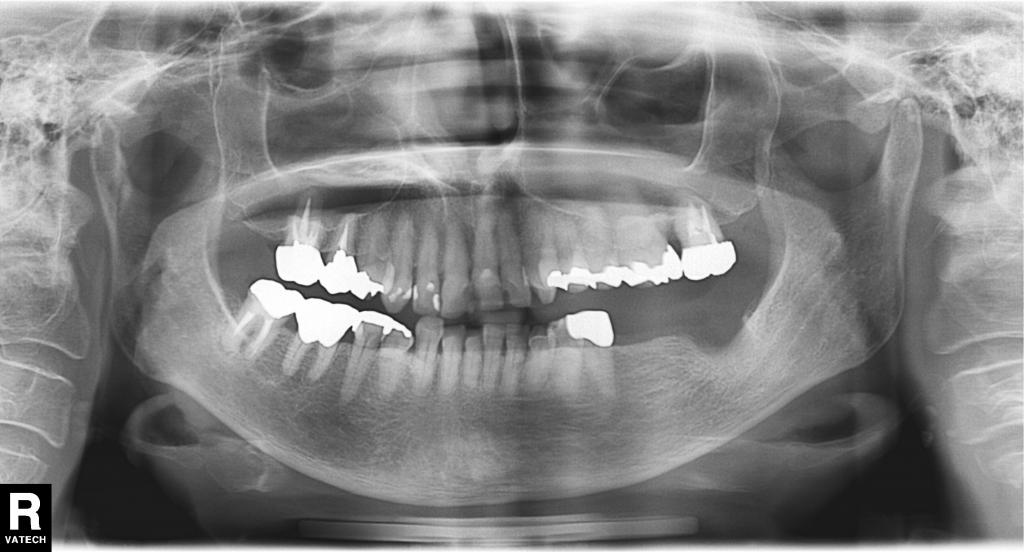

治療前写真

- 重度の歯周病で奥歯をなくされ、「でも入れ歯はしたく無い。インプラント出来ないか?」という相談で来院されました。

- その部分の全体のレントゲン写真です。

左下の骨が大きく吸収していて、通常のインプラントは難しい状態でした。